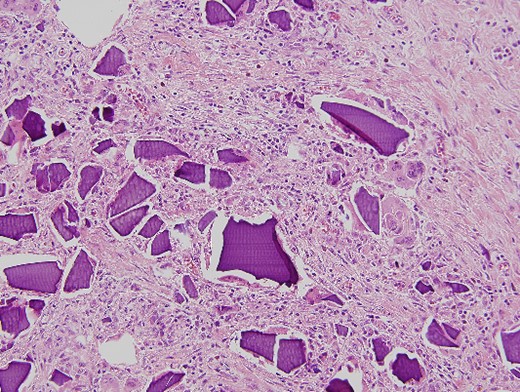

An urgent laparotomy exposing the terminal ileum was performed, signs of intestinal suffering were evident in relation with a thickening and a retraction of the mesoileum at the terminal ileum responsible for the small bowl obstruction. An ileocecal resection with immediate side-to-side ileocolic anastomosis was performed (Fig. 3). Microscopic pathological examination: abundant calcium polystyrene sulfonate crystals along the intestinal wall surrounded by intense inflammatory infiltrate (Figs 4 and 5).

Microscopic pathological examination: abundant calcium polystyrene sulfonate crystals along the intestinal wall surrounded by intense inflammatory infiltrate.

Multinucleate giant cell trying to phagocytize calcium polystyrene crystals.